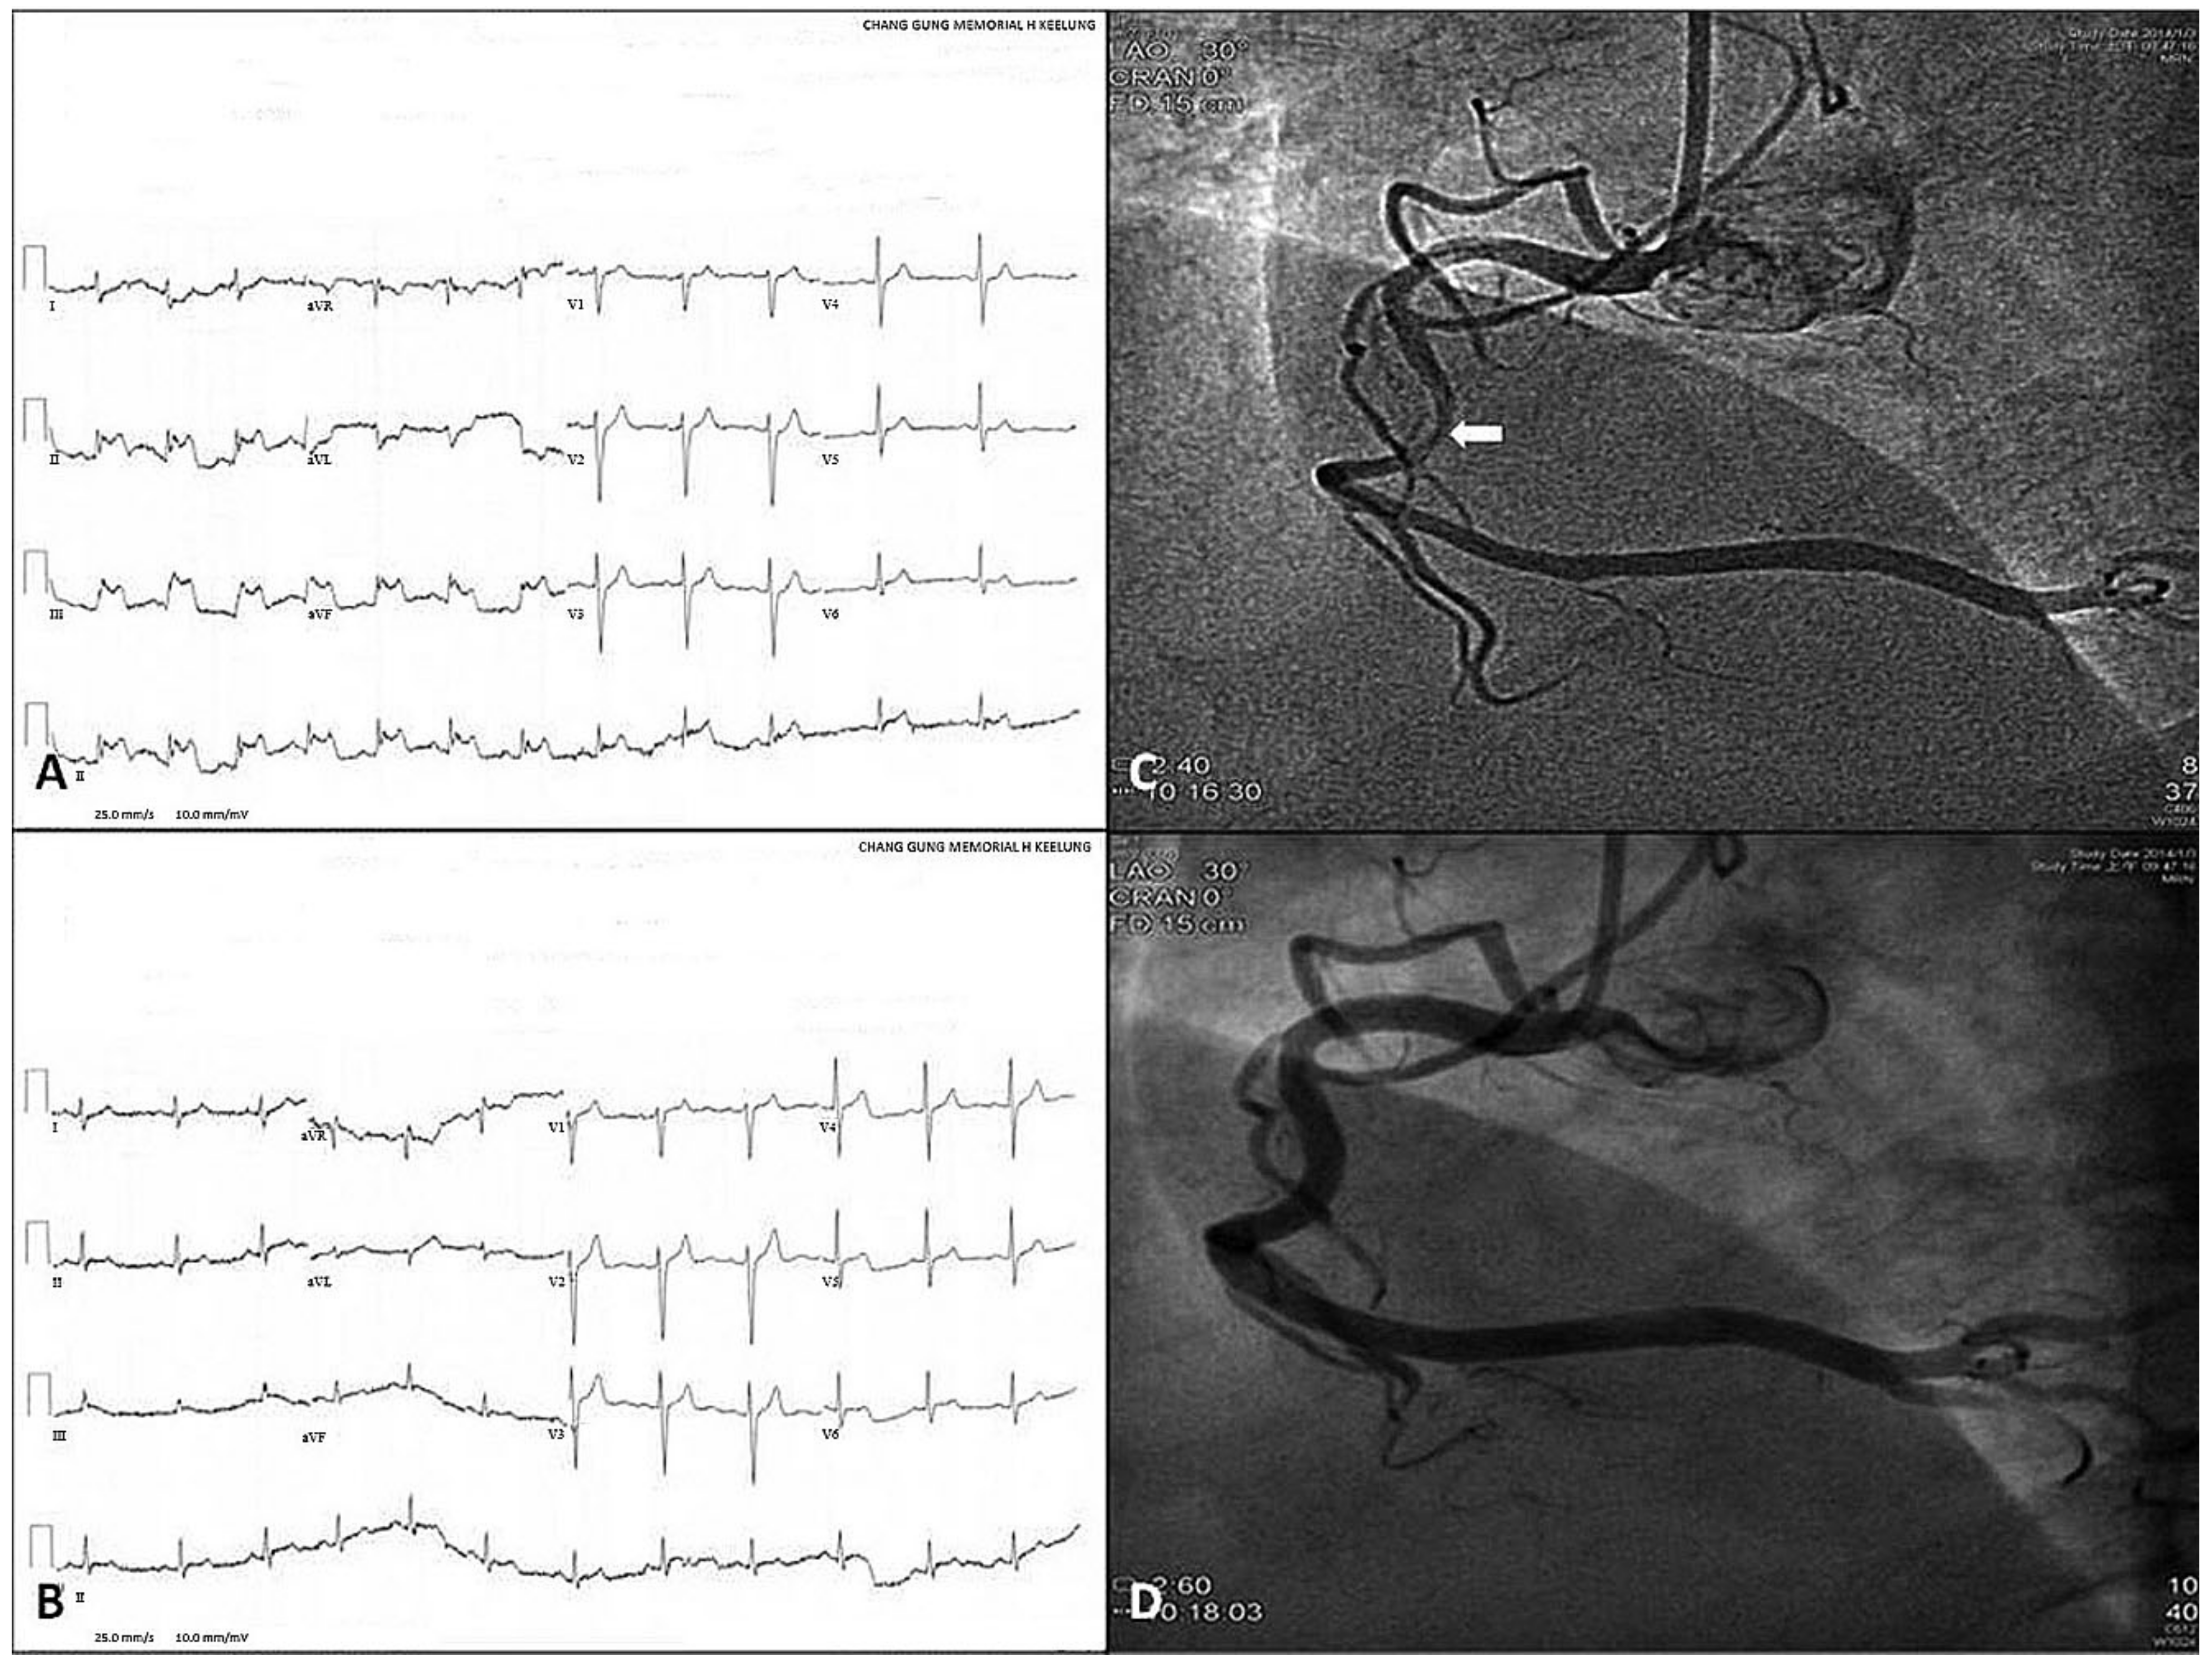

- Hung, M.J.; Cheng, C.W.; Yang, N.I.; Hung, M.Y.; Cherng, W.J. Coronary vasospasm-induced acute coronary syndrome complicated by life-threatening cardiac arrhythmias in patients without hemodynamically significant coronary artery disease. Int. J. Cardiol. 2007, 117, 37–44. [Google Scholar] [CrossRef] [PubMed]